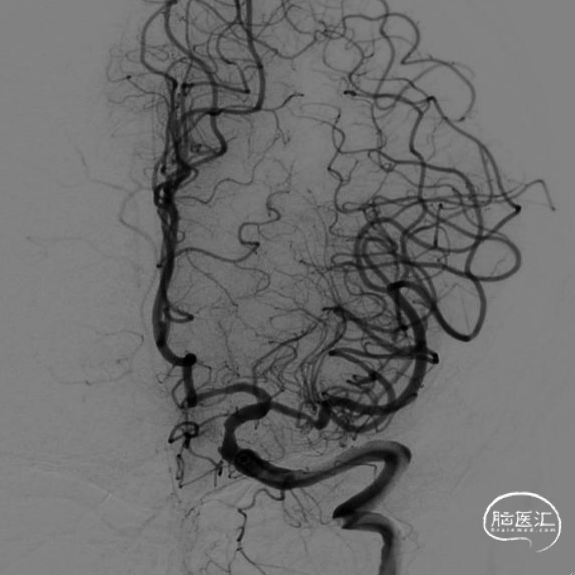

动脉瘤大部填塞后,边支动脉血流完好。